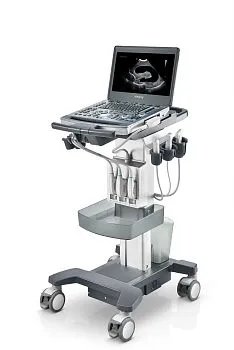

Портативный ультразвуковой аппарат GE Healthcare Logiq e

Особенности системы

Небольшие габариты и малый вес системы позволяют легко использовать её на выезде. С другой стороны Logiq e может быть укомплектован тележкой с тремя активными портами для подключения датчиков, что позволяет полностью воспроизвести функционал полноценной стационарной системы для размещения в кабинете.